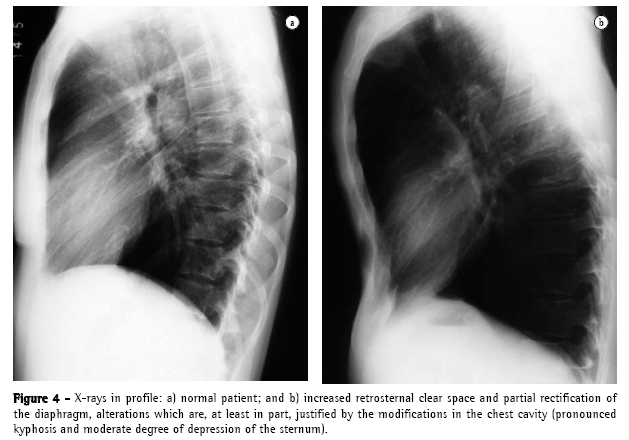

The yield of conventional chest X-ray in the evaluation of emphysema is quite limited. When there is no significant air trapping, the principal alteration is reduction of vasculature, which is only perceived too late in the natural history of the disease, and is an extremely subjective criterion. When there is air trapping (Figures 3 and 4), the criteria are safer, and can be divided into 3 basic groups of alterations,(6,8) presented in Chart 1. When all criteria are present, the diagnosis is definitively confirmed. It should be noted that the increased right chambers of the heart, with reduction of the intrasegmental vasculature, can also be identified in pulmonary arterial hypertension, without emphysema. It should also be noted that bullae are only present in approximately one-third of the cases.

Some authors(15) reported that the length of the right lung and the height of the arch of the hemidiaphragm correlated well with FEV1 and FEV1/vital capacity ratio. In this study, a right lung length of 30 cm or more identified 70% of the patients with respiratory obstruction.(16) However, one author(17) reported that all of these studies presented errors, since they comprise excessive number of patients with chronic respiratory obstruction and, therefore, radiological characteristics of air obstruction receive "disproportionate value in the recognition of emphysema". It was also demonstrated that the sensitivity to chest X-ray is not good, ranging from 24%(18) to 80%.(19) In addition there is considerable intra- and inter-observer variation regarding classical radiological signs.(20) Radiological signs related to vascularization are subject to even greater intra- and inter-observer variation than are signs related to hyperinflation.(19)

Considering that the hemidiaphragm has a surface of approximately 250 cm2, we can calculate that each 4 cm dislocation of the diaphragm determines a dislocation equivalent to approximately 1 L of volume in each lung (2 L, if we consider both lungs). When there is air trapping, the mobility of the diaphragm is limited during expiration. End-expiratory pulmonary volume is significant in the recognition of emphysema. In general, the dislocation of the diaphragm between maximum inspiration and expiration ranges from 3 to 10 cm, corresponding to volumes ranging from 1500 mL to 5000 mL. Cranial dislocation <2 or 3 cm during expiration indicates limited diaphragmatic excursion in the individual with emphysema.(21)

One author comments that the emphysematous pattern defined by the conventional radiological study is only present when the emphysema is so pronounced from the anatomopathological point of view that, in general, pulmonary reserves have already been depleted or pushed to the limit (6,8) A more updated review(22) confirms these propositions:

"If the lungs are mildly affected by emphysema, the X-ray is frequently normal";

"Emphysema can be diagnosed by X-ray when the disease is advanced"; and

"Only half of the patients with emphysema of moderate extent can be diagnosed by chest X-ray."

Both authors suggest that conventional chest X-ray is not a reliable method for the diagnosis or quantification of emphysema.(22) This limitation is so significant that some authors(21) demonstrated that, when conventional radiology managed to diagnose chronic obstructive pulmonary disease, 53% of the patients died within 5 years, and 70% died within 10 years.